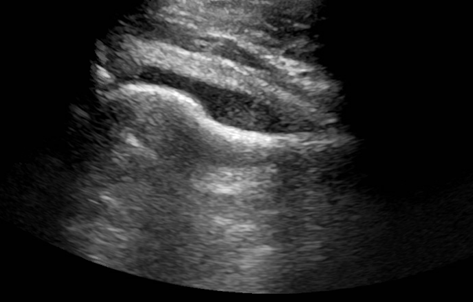

A young man presented to the emergency department with the primary complaint of severe right hip pain persisting for 2 days. This pain began after standing uncomfortably for hours at an event. His right hip was tender to palpation with some erythema and swelling. He had no recent fall or known injury. He denied recent fever, chills, aches, constipation, diarrhea, changes in urinary habits, chest pain, and shortness of breath. An ultrasound (US) of the right hip joint showed moderate amount of effusion (Image 1). Laboratory results also showed an elevated white blood cell count (WBC).

Image 1. US of the right hip joint showing moderate effusion.